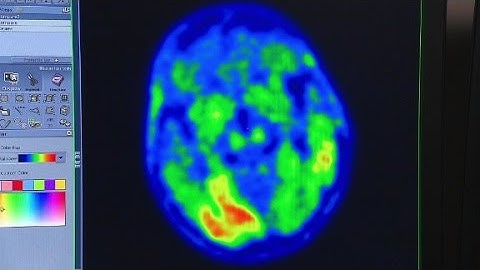

What is tau and what’s it got to do with Alzheimer’s?